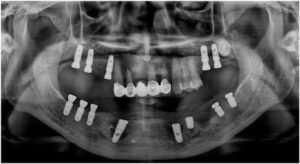

모든 치료가 마무리된

파노라마 사진과

구강 내 사진인데요.

환자분께서는

치료 후 양측 저작이 편안해지고

심미적으로 변한 모습에

만족해하셨습니다.

전 > 후